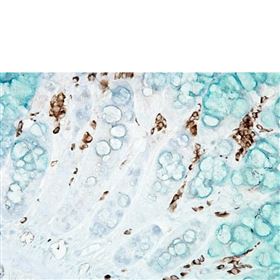

MAIN PHOSPHOLIPID (MPL) OF THERMOPLASMA ACIDOPHILU

MAIN PHOSPHOLIPID (MPL) OF THERMOPLASMA ACIDOPHILU